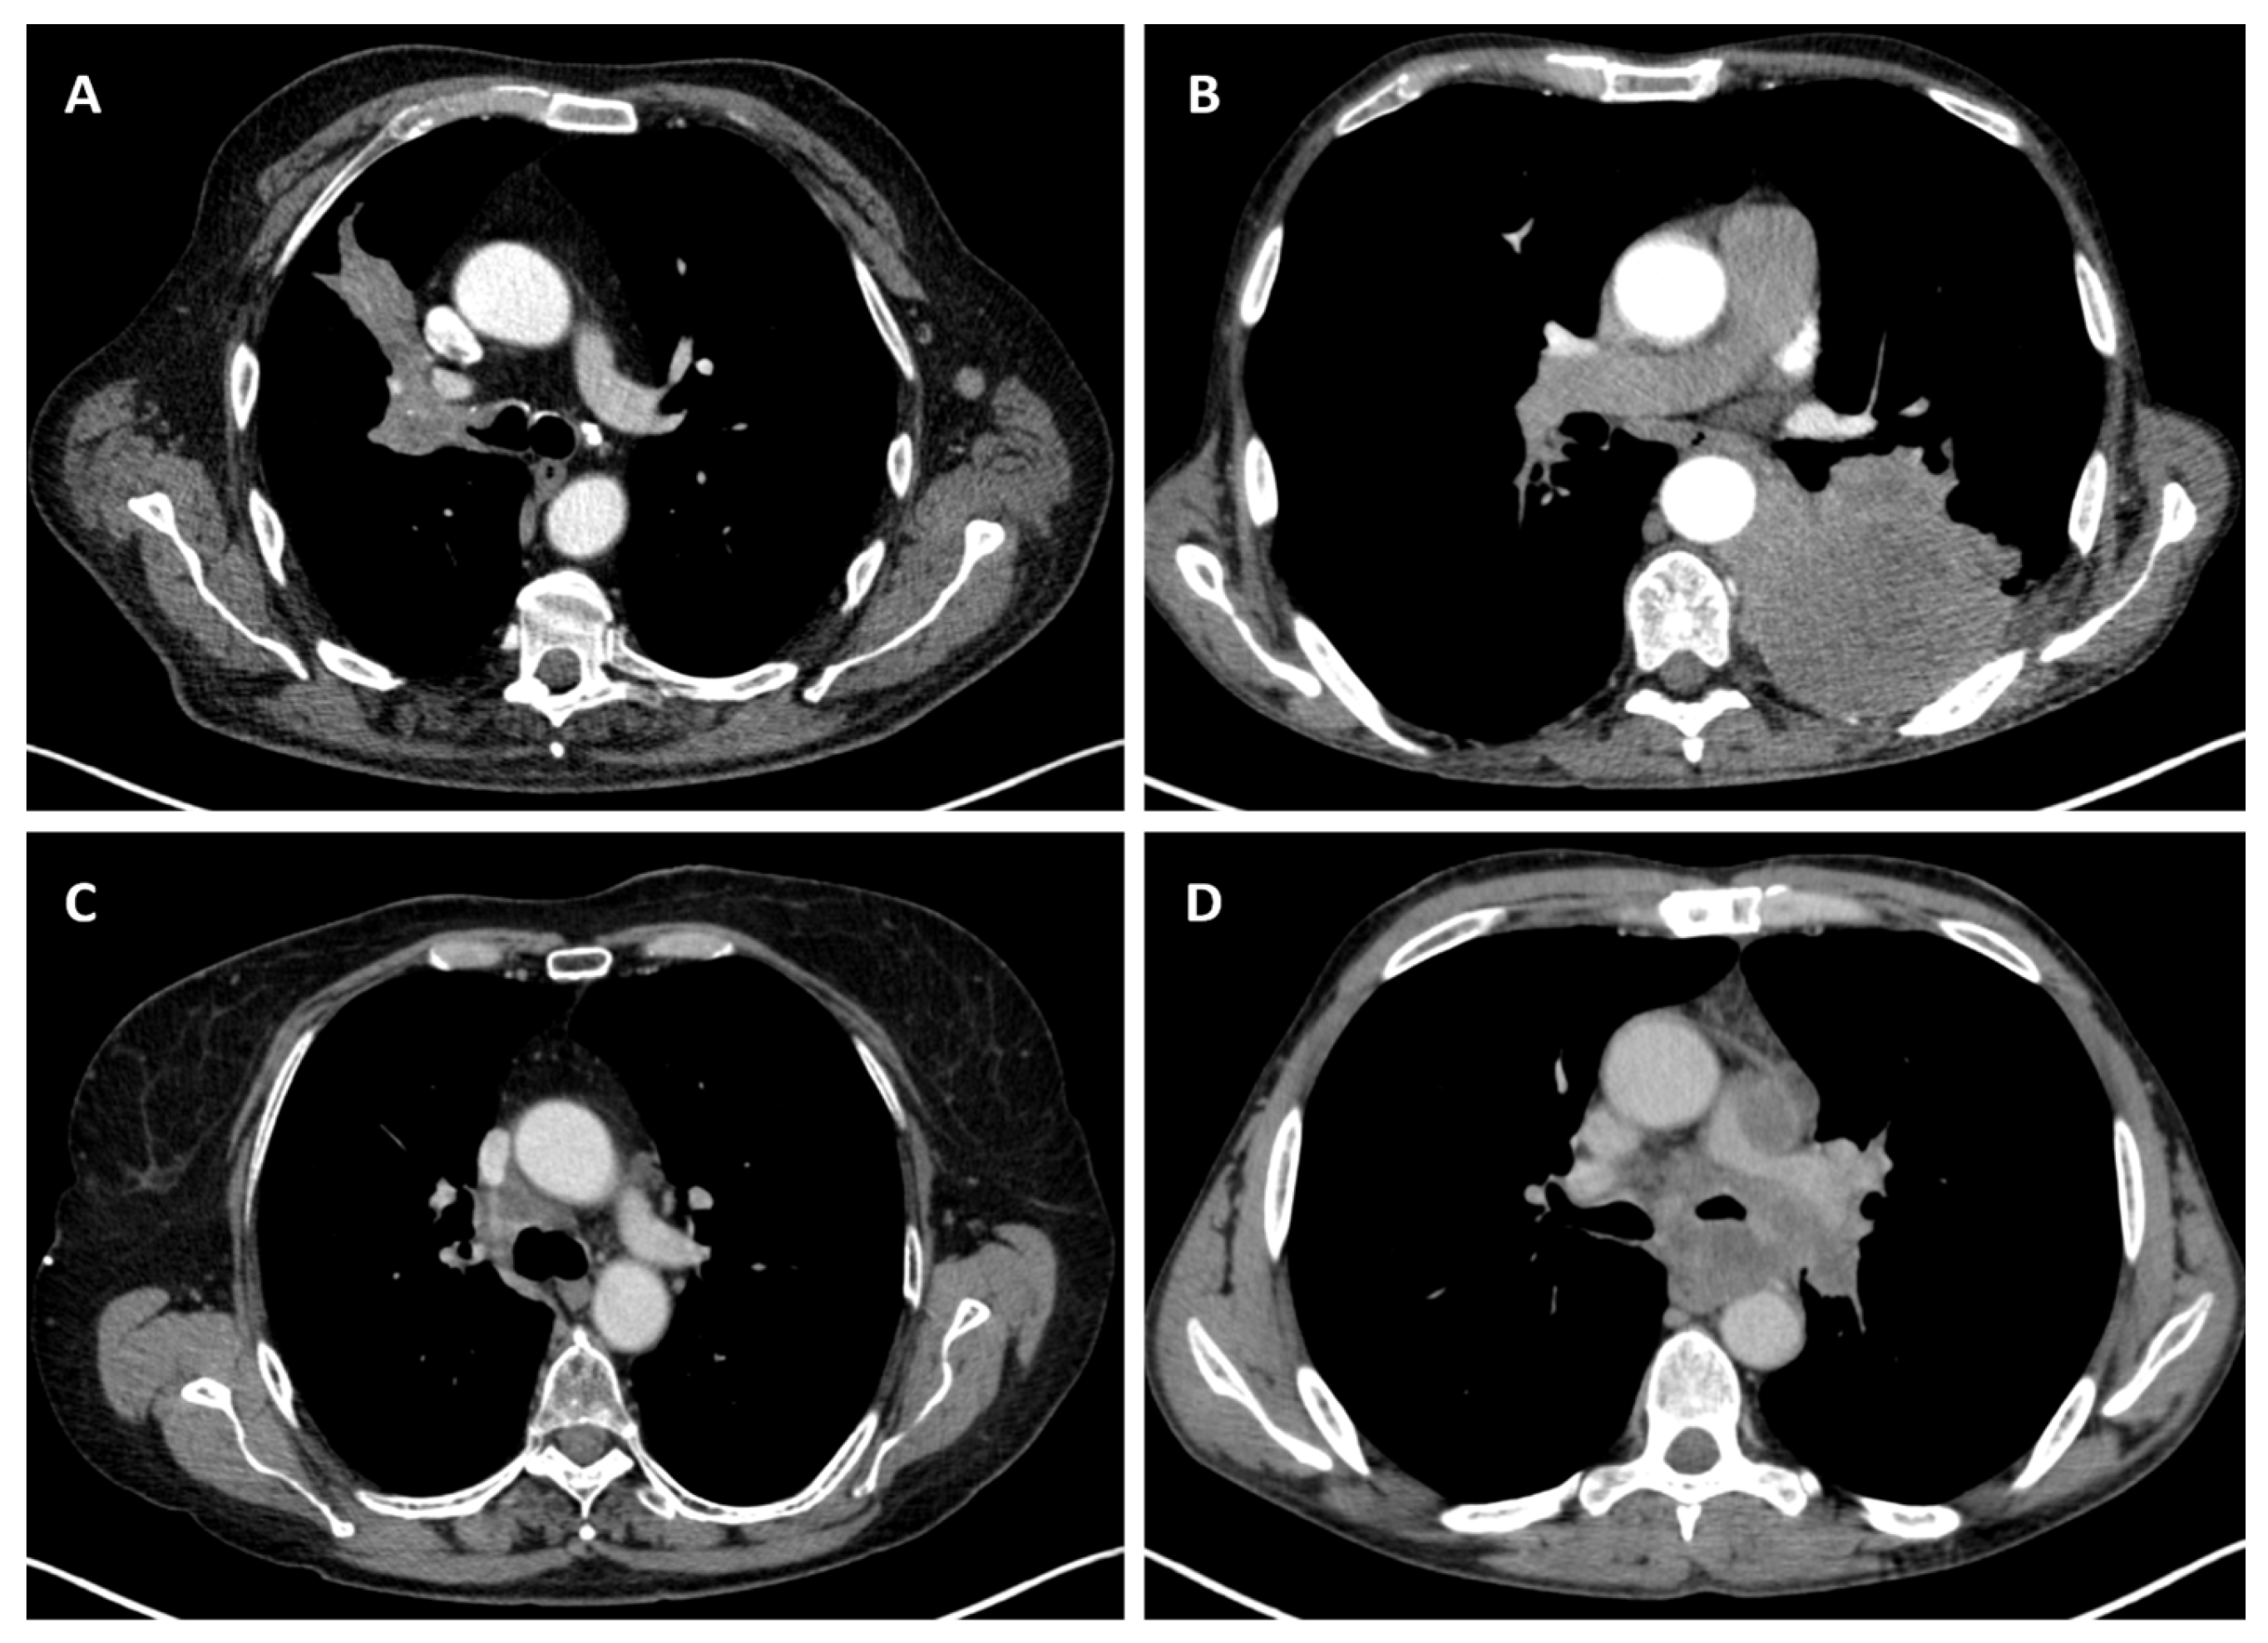

3.2.7. Lymph Node Involvement

4. Discussion